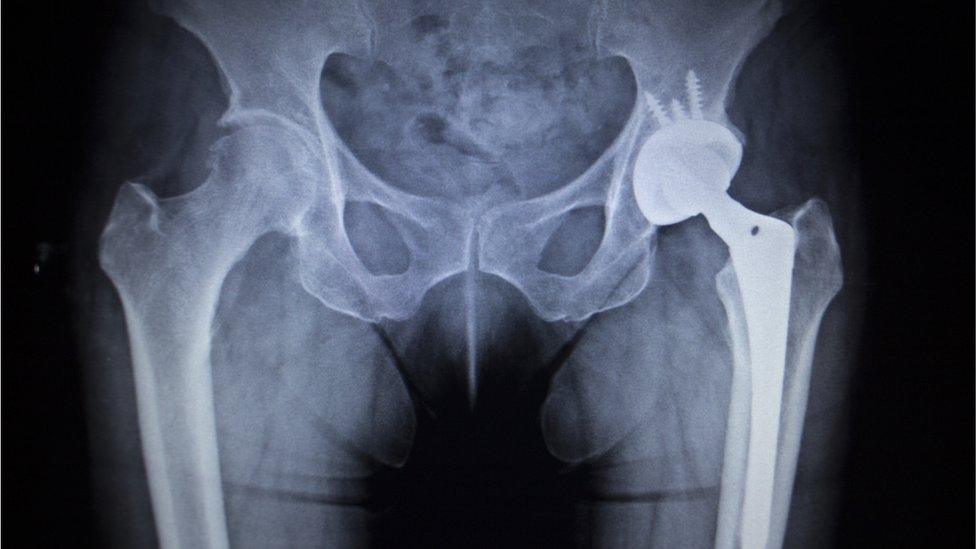

Cost-cutting plans to slash the number of people eligible for hip and knee replacements have been criticised by surgeons.

Three Clinical Commissioning Groups in Worcestershire plan to only treat the most severe cases where pain interferes with daily life and ability to sleep.

Demand for new hips has risen across all ages groups and particularly in the under 60s, NHS figures for England show.

This is mainly because new replacements now last for much longer than before, surgeons say.

But with demand only likely to grow with an ageing population, and the money to pay for them getting increasingly scarce, NHS rationing of hip and knee replacements may well become more common.